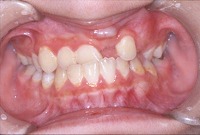

反対咬合と前歯が生えてこない事を主訴に来院された、10歳4か月の男の子です。診断「下顎骨の過成長による骨格性反対咬合で上顎正中の左方偏位と埋伏歯を伴う」1期治療で反対咬合の解消と埋まっていた前歯を牽引しました。